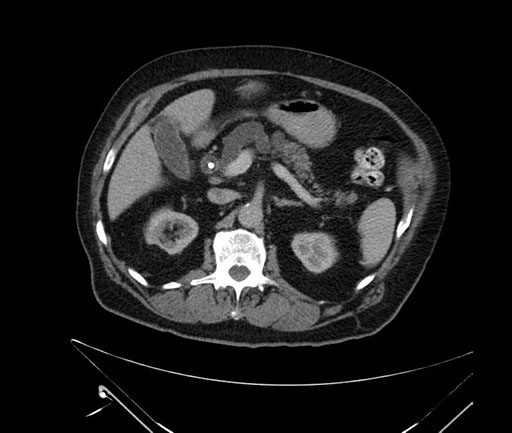

Imaging Analysis

Look through the patient's CT scan to identify any areas of concern for the necessary procedure.

Based on your CT findings, which issue(s) would give reason for "planned slowing down moment(s)" in this case?